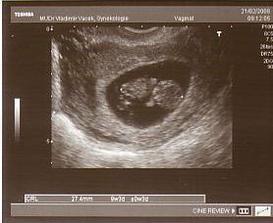

6.2.tak UTZ vyšel na výbornou,až na pana bl... doktora ☹,srdíčko nám buší a máme 8mm